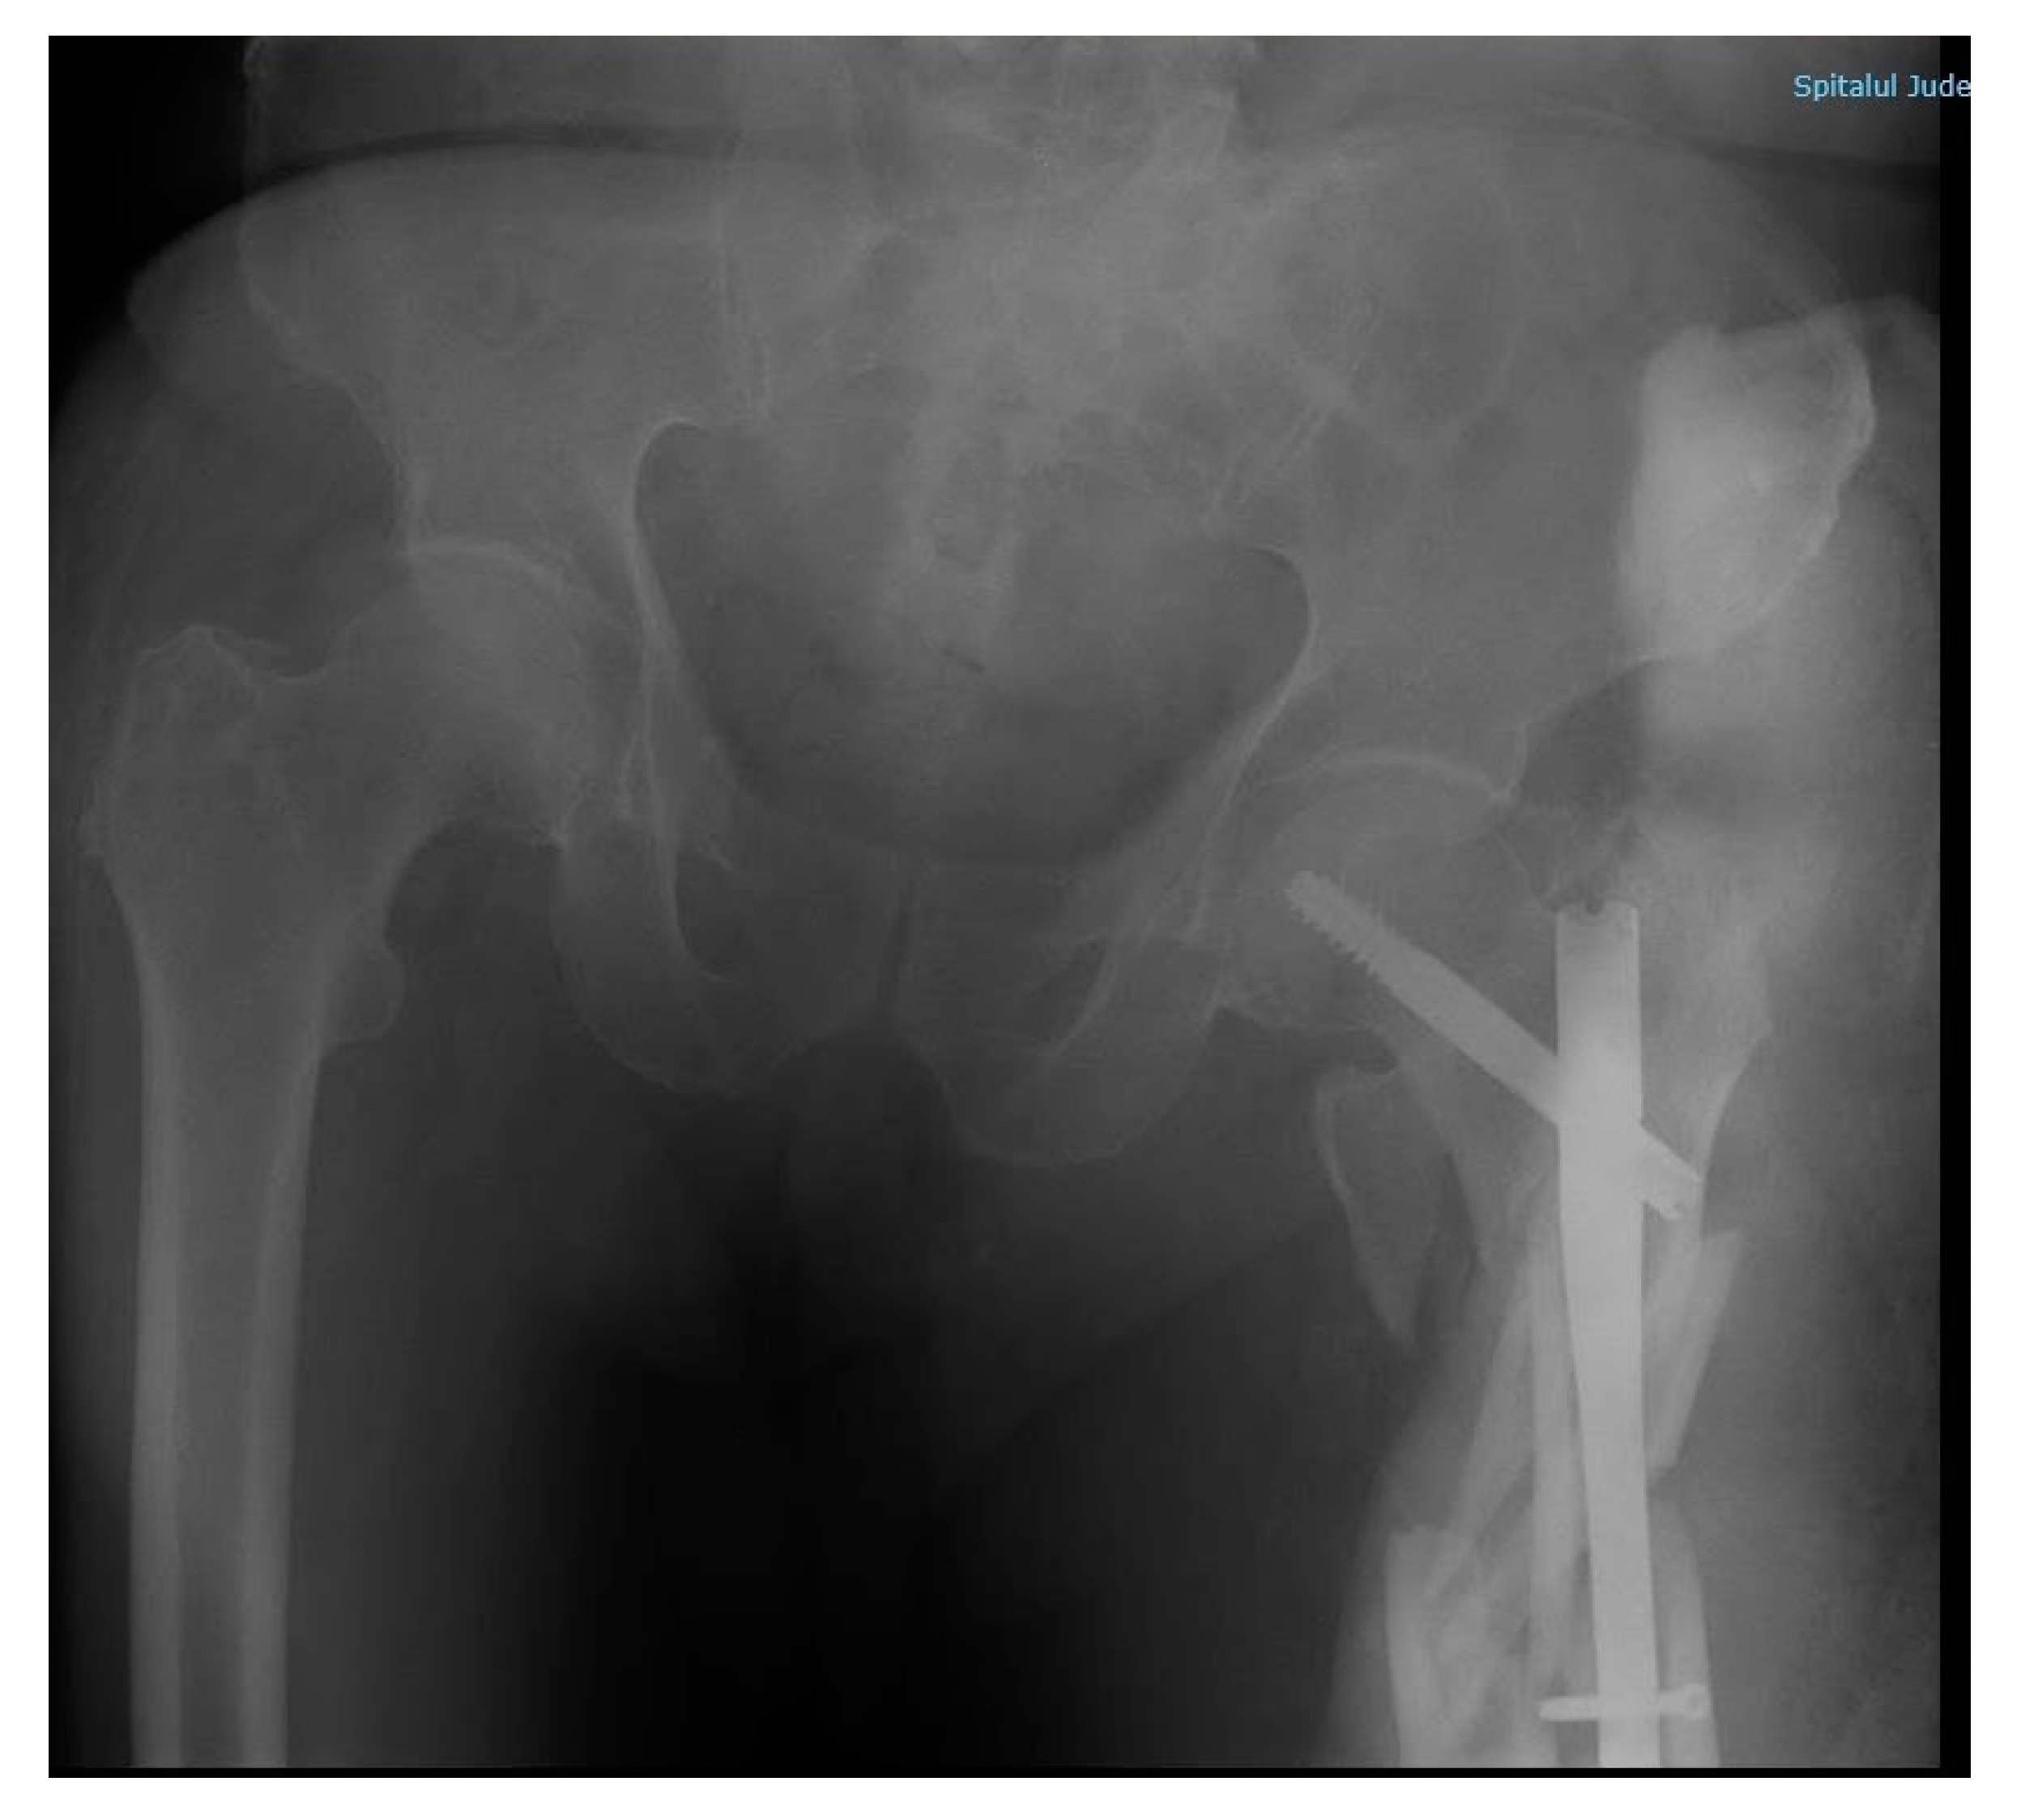

Upon arrival, the patient presented with a 92/55 mmHg blood pressure and SpO2 92%; the surgical examination revealed no cranial, thoracic, or abdominal bleeding. Blood work panel (leucocytes 14.45 × 103/uL; haemoglobin 9.8 g/dL; Htc 29.5%; serum creatinine 1.73 mg/dL; urea 83 mg/dL; TGO 169.3 U/L; TGP 194 U/L) and a left lower limb X-ray were repeated (Figure 7). The X-ray revealed a left femur comminuted fracture with osteosynthesis material destruction. The patient was sedated with propofol and fentanyl, in order to avoid other incidents.

Figure 6. Post-surgery pelvic X-ray, anteroposterior incidence. Description: male subject, urinary catheter. Right hip with minimal narrowing of the joint space. Left hip with osteosynthesis material (intramedullary rod) in the proximal segment of the femur with distal nailing. Bone fragment with dorsal and internal displacement. Coxo-femural spaces maintained. Acetabular surfaces with sclerosis.

Figure 7. Hip X-ray after 3-m height fall, anteroposterior incidence. Description: male subject. Right hip with minimally narrowed joint space. Left hip in the ⅓ proximal of the femur with osteosynthesis material (femoral rod distally nailed) slightly moved, degraded. Comminuted fracture with bone fragments misaligned in the proximal diaphysis of the left femur, with angulation of fragments. Loss of contour between normally continuous line from medial edge of femoral neck and inferior edge of the superior pubic ramus. Minimally impacted left femoral neck.